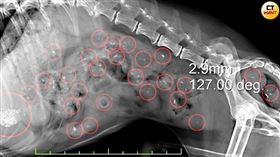

老病犬胃滿滿異物 西莎藏63顆塑膠和石頭

國際寵物食品品牌「西莎」靠著「餐餐西莎寵愛牠」廣告詞...